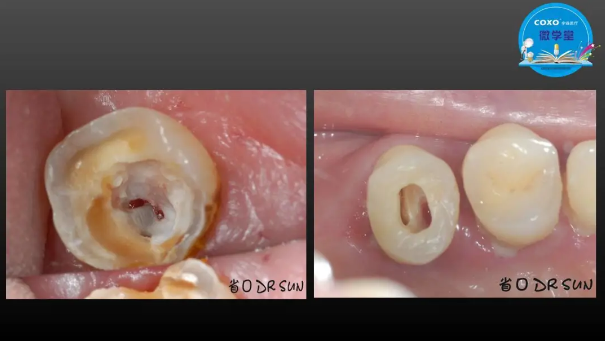

主任醫(yī)師,牙體牙髓副主任, 廣東省口腔醫(yī)院牙體牙髓科 主任醫(yī)師。2003年碩士研究生畢業(yè),研究方向?yàn)檠荔w牙髓病學(xué),擅長(zhǎng)于牙體牙髓病的診斷、齲齒、牙髓炎、根尖周病的治療以及前牙美容修復(fù)。